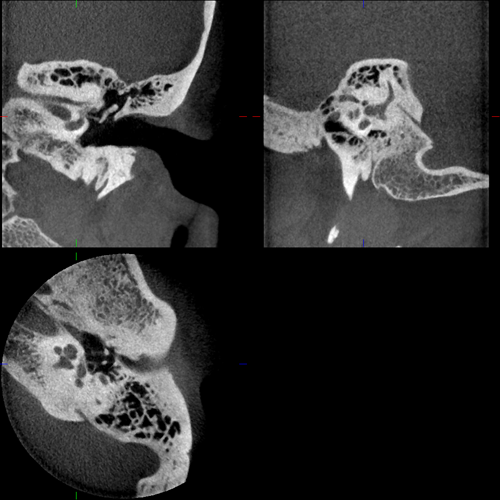

Ambossarrosion mit Stapesprothese Stapesprothese Teflon (Causse) PORP auf Stapes PORP Titan auf Stapes PORP PORP Titan disloziiert Otosklerose Otoskleroseherd TORP Pauke nicht belüftet TORP unter Knorpelinsel disl.